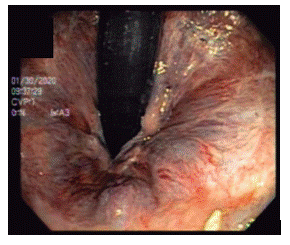

Se utilizaron endoscopios Olympus GIF-100 y Olympus GIF-Q-140, y sets de ligadura múltiple de Boston Scientific y Cook, los mismos que para ligadura de várices esofágicas. En retroflexión en recto, se identificaron las hemorroides (Fig. 1) y se realizó aspiración y colocación de bandas elásticas por lo menos 5 mm proximal a la línea pectínea (Fig. 2).

Figura 1. Hemorroides internas grado II, visión en retroflexión en recto.